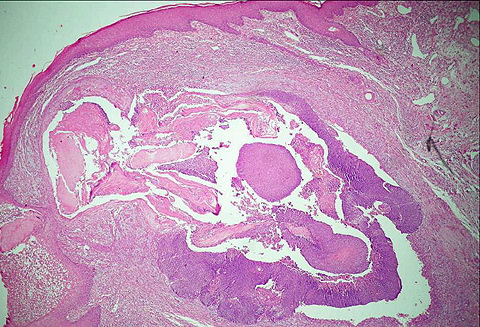

Pilomatricoma--perforating pilomatricoma = ورم أم الشعرة الثاقب